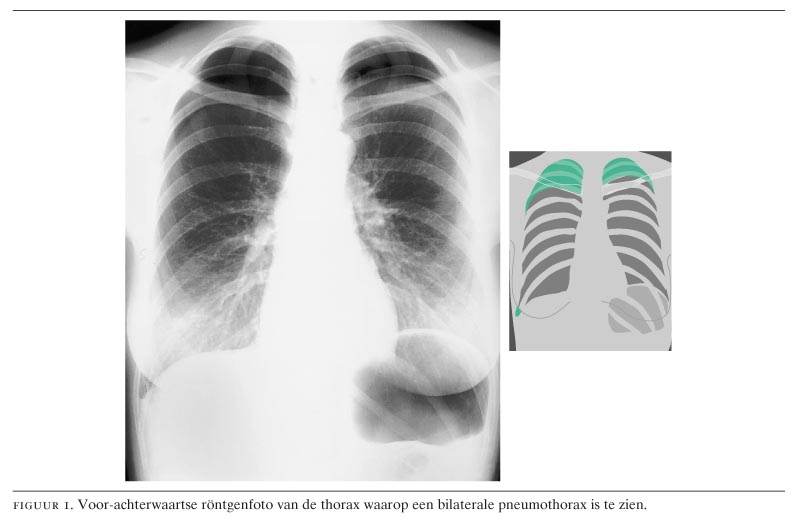

Bij lichamelijk onderzoek zagen wij een dyspnoïsche vrouw met een bloeddruk van 115/70 mmHg en een polsfrequentie van 100/min. Er waren over de thorax hypersonore percussie en verminderd ademgeruis beiderzijds. Aanvullend werd een thoraxfoto gemaakt, waarop een bilaterale pneumothorax te zien was (figuur 1). Aan de hand van deze bevinding werd patiënte opgenomen en werden beiderzijds thoraxdrains ingebracht waarop de kortademigheid verdween. Na twee dagen waren beide longen weer goed ontplooid en werden de thoraxdrains verwijderd. Patiënte kon in goede conditie het ziekenhuis verlaten.